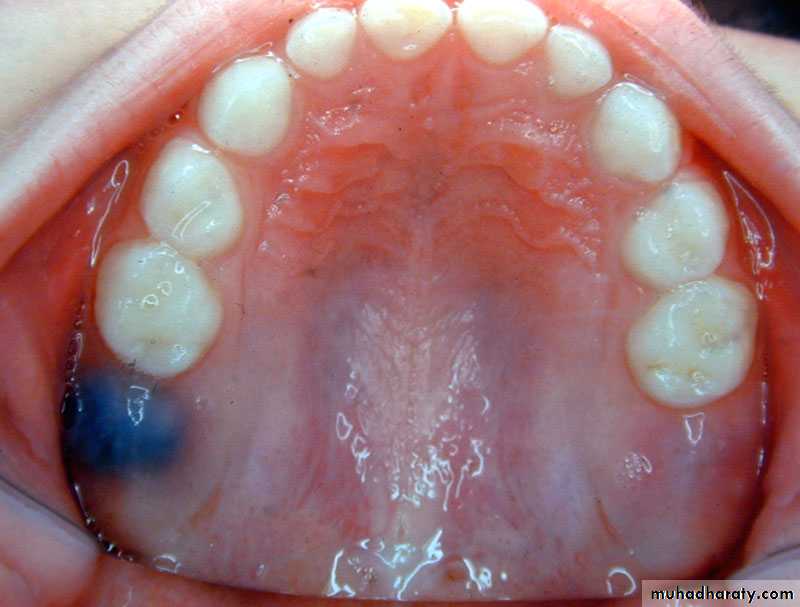

Morphological difference between primary and permanent teeth

The crowns of primary teeth :

are shorter

have a narrower occlusal table

have a more pronounced cervical constriction

have thinner enamel and dentin layers

Keys to differentiating primary and permanent teeth:

Color primary teeth white and opaque

Size and contoursDepth of anatomy

Age of child

Location of teeth (counting)